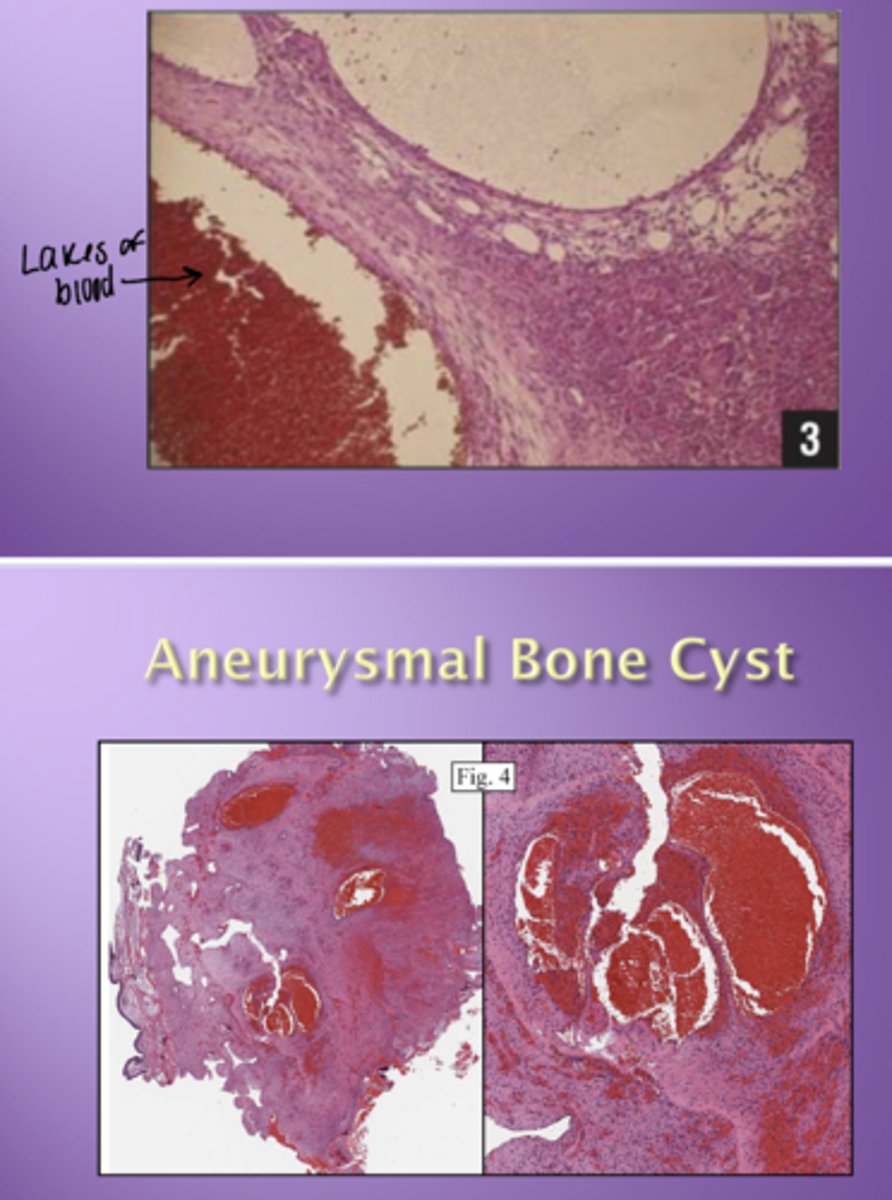

Aneurysmal bone cyst - histology

Lakes of blood

- No endothelium around spaces